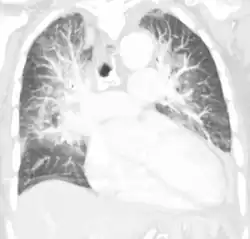

Various laboratory tests (CBC, troponin, BNP, etc.) and imaging studies (chest x-ray, CT scan, ultrasound) are often used to diagnose and classify the cause of pulmonary edema.[4][5][6]

Chest X-ray has been used for many years to diagnose pulmonary edema due to its wide availability and relatively cheap cost.[4] A chest X-ray will show fluid in the alveolar walls, Kerley B lines, increased vascular shadowing in a classical batwing peri-hilum pattern, upper lobe diversion (biased blood flow to the superior parts instead of inferior parts of the lung), and possibly pleural effusions. In contrast, patchy alveolar infiltrates are more typically associated with noncardiogenic edema.[3]

Lung ultrasounds, employed by a healthcare provider at the point of care, is also a useful tool to diagnose pulmonary edema; not only is it accurate, but it may quantify the degree of lung water, track changes over time, and differentiate between cardiogenic and non-cardiogenic edema.[36] Lung ultrasound is recommended as the first-line method due to its wide availability, ability to be performed bedside, and wide diagnostic utility for other similar diseases.[4]

Especially in the case of cardiogenic pulmonary edema, urgent echocardiography may strengthen the diagnosis by demonstrating impaired left ventricular function, high central venous pressures and high pulmonary artery pressures leading to pulmonary edema.